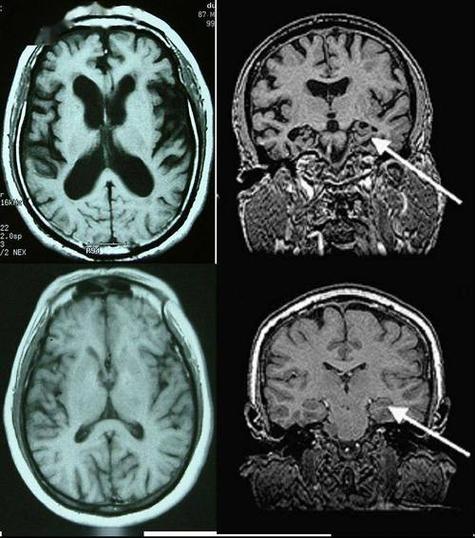

CT/MRI(尤其是DWI序列MRI):是诊断脑梗的“金标准”,它们通过显示解剖结构的变化来发现梗死病灶,在脑梗发生的早期(几小时内),MRI就能非常敏感地检测到脑组织的水肿和细胞坏死,从而明确梗死的部位、范围和大小,这是形态学上的诊断。

PET/CT:主要显示的是细胞功能和代谢情况,它通过注射放射性示踪剂,来观察身体不同部位(包括大脑)的葡萄糖代谢、血流、蛋白质合成等情况,这是功能性的诊断。